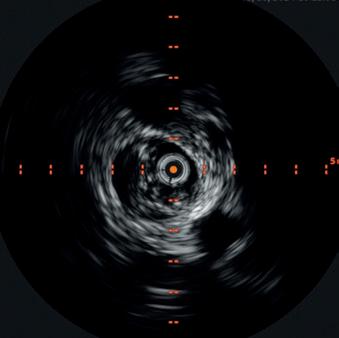

The Shockwave E8 experience: Featuring the new Shockwave peripheral IVL workhorse

Paul J. Foley III, MD, a vascular surgeon and director of the non-invasive vascular lab at Doylestown Hospital in Doylestown, Pennsylvania, and adjunct associate professor of surgery at the University of Pennsylvania in Philadelphia, discusses the virtues of the new Shockwave E8 IVL catheter.

Endovascular interventions for chronic limb-threatening ischemia (CLTI) are technically demanding endeavors. Multi-level arterial disease, long-length lesions and other complex plaque characteristics are frequently encountered when treating these patients.1,2 Calcium modification with intravascular lithotripsy (IVL) has emerged as a useful tool to combat the challenges of calcified lesions with the goal of maximizing luminal gain to achieve improved endovascular outcomes, both radiographically and clinically.3 Balanced lithotripsy pulse delivery across longer-length lesions, as well as effectively treating calcified disease across multiple arterial beds, can be laborious considering the number of available pulses and the length of the IVL catheter relative to the extent of disease.

The following case highlights the versatility of the Shockwave E8 IVL catheter to treat long-length lesions in two tibial arteries.

A 78-year-old man who resides in Uzbekistan presented to the office with CLTI of the left lower extremity manifested by a non-healing gangrenous left toe ulcer and associated rest pain (Figure 1). He was initially evaluated by providers in his home country and had a recent arteriogram in Uzbekistan demonstrating severe multi-level arterial disease in the left lower extremity,

An arteriogram of the left lower extremity was performed via antegrade left common femoral artery access based on preoperative review of the lower extremity arteriogram from Uzbekistan. Scattered non-calcified plaque with moderate to high-grade stenoses were identified in the proximal and mid superficial femoral artery. Diffuse severe calcified tibial artery disease was identified. There was a long segment stenosis of the proximal and mid posterior tibial artery coupled with a more distal occlusion. The proximal peroneal artery was calcified and occluded with distal reconstitution identified. There was complete occlusion of the anterior tibial artery (Figure 2).

Shockwave E8 3mm x 80mm to the posterior tibial artery

The posterior tibial artery was successfully crossed first. The long-length posterior tibial artery disease was treated with a Shockwave E8 3.0mm x 80mm IVL catheter, with no pre-dilatation required. A total of 200 pulses were delivered along the length of the posterior tibial artery (Figure 3).

Shockwave E8 3mm x 80mm to the peroneal artery

Following this, the peroneal artery occlusion was successfully crossed. The longlength peroneal artery disease was treated with the same Shockwave E8 3mm x 80mm IVL catheter also with no pre-dilatation required. The remaining 200 pulses were

delivered across the length of the peroneal artery disease (Figure 3).